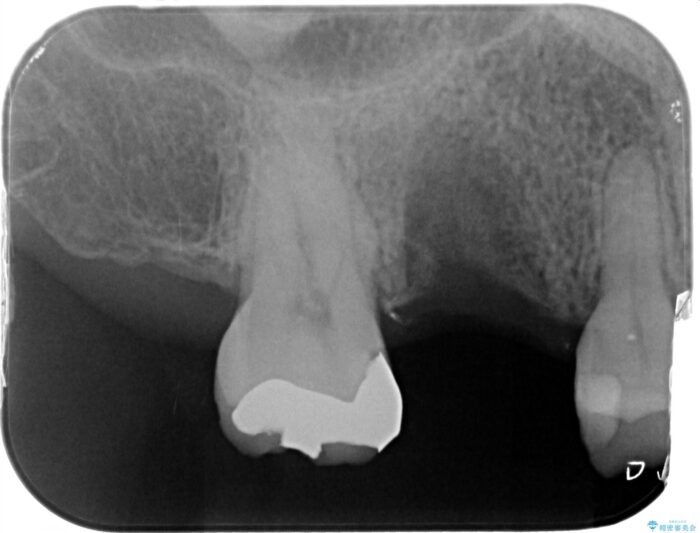

虫歯の悪化により奥歯を失った患者様です。 咬合機能の回復を求めてご相談にいらっしゃいました。

ブリッジ、インプラント、入れ歯による長短所のご説明を行い、インプラント治療を進めていくこととなりました。